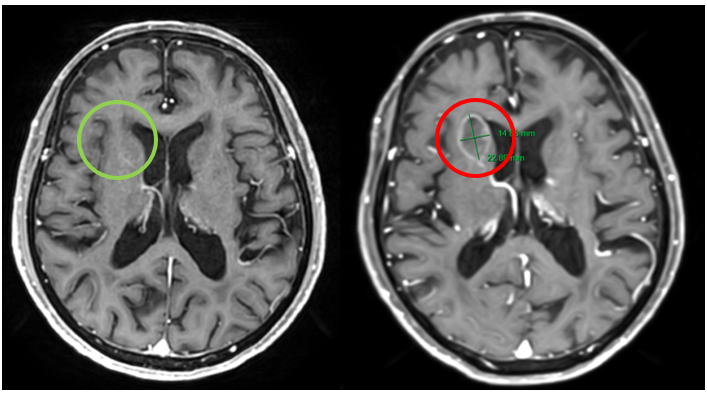

Bệnh nhân được chụp Cộng hưởng từ sọ não phát hiện ổ di căn trên thùy trán phải cạnh sừng trán não thất bên. Bệnh nhân và gia đình có nguyện vọng không tiếp tục điều trị và chuyển sang chăm sóc giảm nhẹ.

Hình 8. Hình ảnh não không có khối choán chỗ trong thời gian điều trị (mũi tên xanh) và não xuất hiện khối u di căn não thùy trán phải cạnh sừng trán não thất bên, kích thước 14x22 mm sau khi bỏ điều trị 3 tháng (mũi tên đỏ), trên phim cộng hưởng từ sọ não tại mặt phẳng axial.